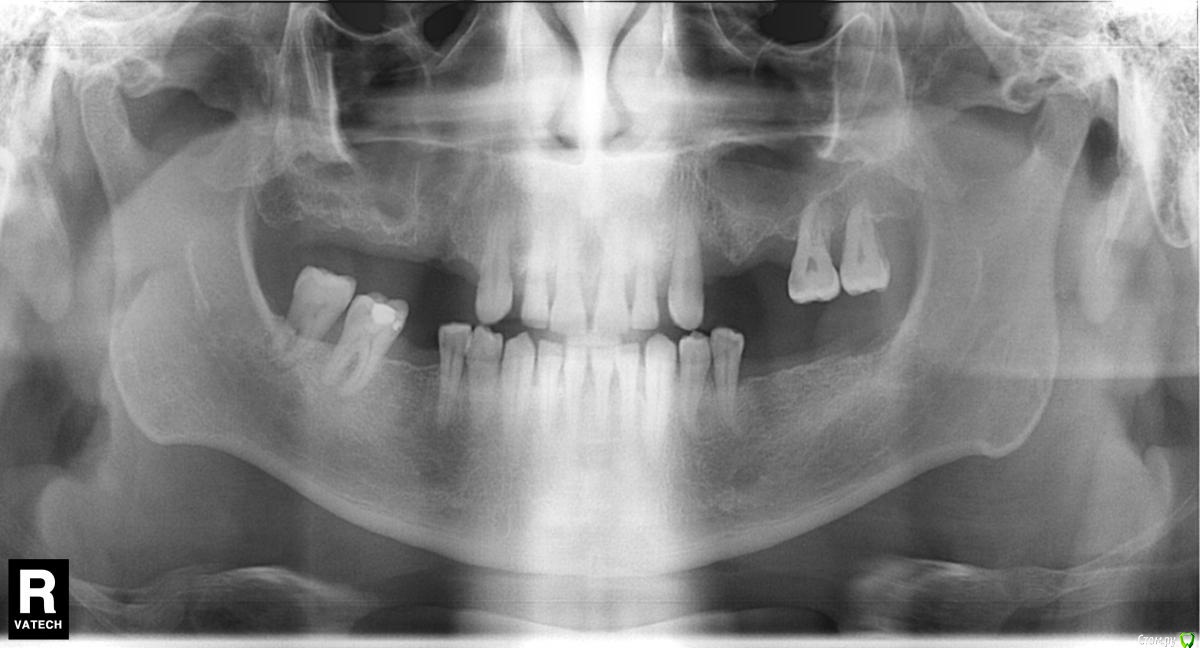

DESS Опубликовано 31 августа, 2015 Поделиться Опубликовано 31 августа, 2015 Добрый день, совсем запустил зубы...но сейчас совсем прижало...и надо исправлять положение...могли бы вы подсказать...к чему готовиться... Ссылка на комментарий